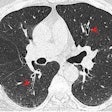

Novel study investigates impact of marijuana on lungs